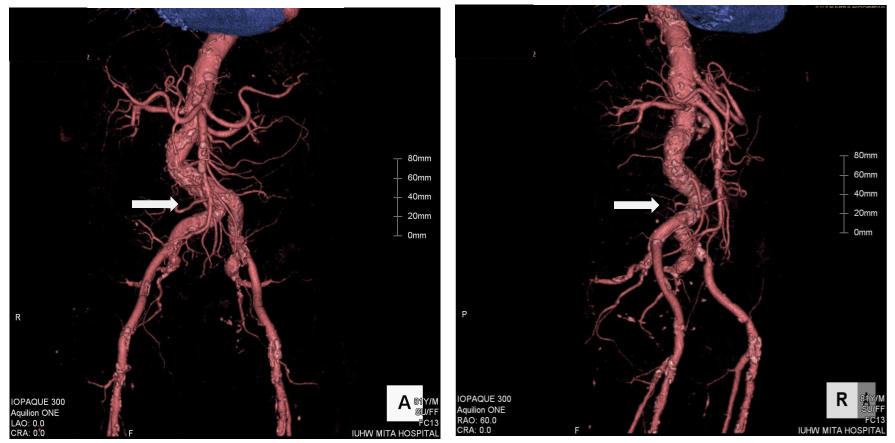

Figure 1 Three-dimensional image from enhanced computed tomography. The white arrows indicate significant tortuosity of the right common iliac artery. Left: antero-posterior projection. Right: right anterior-oblique projection.

An 81-year old man had been attending a physician at our hospital for several years, because of type II diabetes mellitus, hypertension, and chronic kidney disease. On one regular visit to the doctor, sudden syncope and collapse within the hospital required him to be admitted to the department of internal medicine. The patient recovered consciousness several minutes later and no apparent neurological abnormality could be detected. Cardiovascular examination identified no significant heart murmur. Blood tests showed no evidence of myocardial enzyme leakage, electrolyte disturbance, inflammation, or significant anemia that might be associated with syncope, except for the fact that the troponin I level was just above the upper normal limit (0.11ng/mL). The electrocardiogram also showed no specific changes suggestive of an acute coronary syndrome (ACS). The chest X-ray depicted a status of mild congestion, and echocardiography showed signs of mild hypokinesis of the posterior wall. Brain computed tomography (CT) showed no evidence of fresh infarction or hemorrhage at this point. Enhanced CT from chest to pelvis did not indicate any evidence of aortic dissection or aneurysmal rupture, but there was significant tortuosity of the right common iliac artery and the abdominal aorta below the renal arteries, with severe calcification (Figure 1). The next day’s blood test, however, showed significant increases in the levels of CK (2823IU/L), AST (433IU/L), LDH (1231IU/L), and WBC (132.1×100/µL), signifying the development of acute myocardial infarction. The coronary angiography (CAG) was performed via the right femoral artery, using 5F diagnostic catheters, JL5.0 and JR4, and showed a 90% stenosis in the left anterior descending artery (LAD)#6-7, with TIMI grade III flow, and a total occlusion in the right coronary artery (RCA)#2, with a relatively steep angulations (Figure 2). Accordingly, PCI was performed, treating the RCA occlusion as a culprit on the same day. Since the patient suffered from chronic kidney disease, as indicated by the high creatinine value (1.85mg/dL) and low estimated glomerular filtration rate (21.5mL/min/1.73m2), we selected the right femoral artery for access, in order to preserve the radial arteries for shunts in the case of hemodialysis. Although the left femoral artery was also considered as a candidate for access, the weak pulsation of both left popliteal and dorsal arteries kept us from choosing it. Even though the enhanced CT indicated this case as a high complicated case about its vessel tortuosity, we continued the procedure with disregard for this information at this point. A 7F super-long sheath was inserted in order to elongate the tortuosity of the common iliac artery, but the sheath became kinked at the tortuous point. Consequently, the guiding catheters could not be manipulated effectively, because of the tight constriction of each catheter by the sheath. We sized down the catheter from 7 F to 5F (7F JR4.0, SAL0.75, and AL1.0, 6F AL1.0, and 5F JR4.0) so as to allow more space, but this was unsuccessful. Finally, we decided to change the access site to the right brachial artery with a 6F sheath, and we selected a 6F EBU3.5 as a guiding catheter. As we carefully manipulated the catheter, in which the Radiocast® Guide wire (TERUMO, Tokyo, Japan) was still inserted, the tip of the catheter passed into the RCA, though not very deeply. The ULTIMATEbros3® guidewire (ASAHI INTECC, Aichi, Japan) was successfully advanced to #4AV with support from a microcatheter, (Finecross® MG, TERUMO, Tokyo, Japan), after an attempt to cross the lesion witha floppy guidewire had failed (Joker®, Japan Lifeline, Tokyo, Japan) (Figure 3). The lesion was then dilated using a 1.2mm semi-compliant balloon (TENKU®, ST. JUDE MEDICAL, St Paul, MN, USA) followed by a 2.5mm balloon (Lacrosse LAXA®, GOODMAN, Aichi, Japan). At this point, we established that there was recovery flow of TIMI II, with huge amounts of floating thrombus. Unfortunately, the aspiration was completely unsuccessful, so we decided to compress the thrombus as far as possible using a large-sized balloon. From the occlusion site to distal portion#3, the vessel was entirely dilated by a 3.5mm semi-compliant balloon (Sprinter® legend RX, Medtronic, Minneapolis, MN, USA), followed by a 5.0mm non-compliant balloon (NC Quantum Apex®, Boston Scientific, Natick, MA, USA). Finally, we determined that it would be better to terminate the procedure at this point without any stent deployment, because of the abundance of fresh thrombus throughout the RCA (Figure 4).